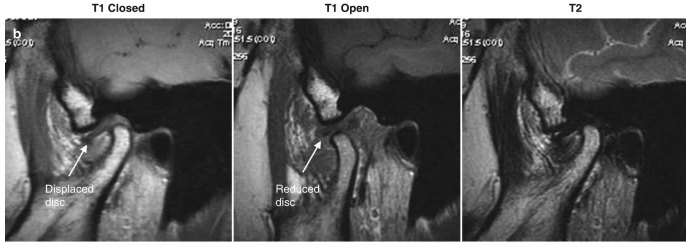

Explain MRI. what is disk position

Normal disk position